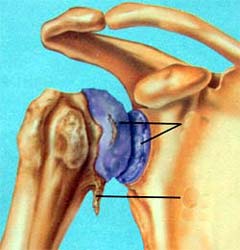

骨性关节炎造成的肩关节软骨破坏,骨刺形成 肱骨头粉碎骨折

全肩关节置换术后示意图 肱骨头置换后X线片